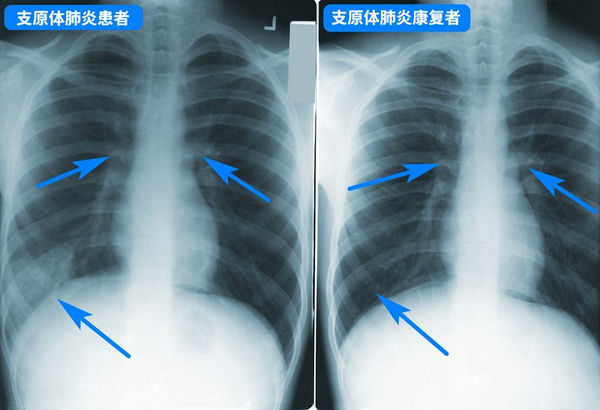

支原體肺炎胸透片

支原體肺炎一般并不嚴重,但要小心預防病情加重,盡早就醫,如持續發燒5天以上、劇烈咳嗽不止,則一定要就醫,以評估肺部是否受影響,以及是否存在并發癥。治療兒童支原體肺炎一般用阿奇霉素等大環內酯類藥物,但因為亞洲地區濫用藥物引起的耐藥性問題,很可能效果不佳,需要在治療過程中換藥,具體應該遵醫囑。